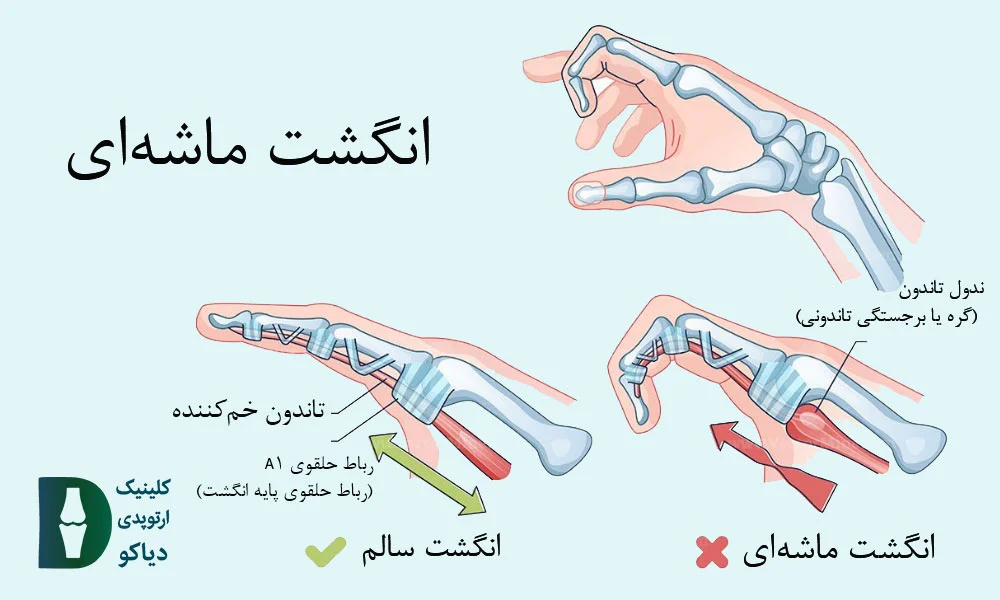

انگشت ماشهای در بزرگسالان معمولاً بهدلیل التهاب مزمن غلاف تاندون و تنگی در ناحیه رباط حلقوی A1 رخ میدهد و بیشتر انگشت حلقه یا میانی را درگیر میکند.

در بزرگسالان، انگشت ماشهای اغلب بهدلیل التهاب و ضخیمشدن غلاف تاندون خمکننده (بهویژه در ناحیهی A1 pulley ) ایجاد میشود؛ وضعیتی که باعث گیر کردن تاندون در مسیر حرکتش شده و هنگام باز یا بسته کردن انگشت، احساس قفلشدگی، صدای تق یا درد بهوجود میآورد.

درجهبندی شدت انگشت ماشهای (Green Classification):

برای ارزیابی شدت انگشت ماشهای، از سیستم درجهبندی Green استفاده میشود. این دستهبندی، بر اساس میزان قفلشدگی انگشت و توانایی فرد در خم یا صافکردن آن طراحی شده و راهنمای مناسبی برای انتخاب روش درمانی است (منبع).

در ادامه، انواع گریدها را بررسی میکنیم.

درد و حساسیت در کف دست بدون مشاهده قفلشدگی در معاینه. |

انگشت هنگام حرکت قفل میکند اما بیمار قادر به صافکردن فعال آن است. |

انگشت در حالت خمشده قفل میماند و برای صافشدن نیاز به کمک دست دیگر دارد. |

انگشت قفلشده است و بیمار قادر به خمکردن فعال آن نیست. |

انگشت در وضعیت خم باقی مانده و دچار محدودیت دائمی حرکت شده است. |

در بیماران با گرید 2 و 3a، که انگشت هنگام حرکت دچار قفلشدگی میشود ولی هنوز قابلیت صافشدن دارد (چه بهصورت فعال یا با کمک دست دیگر)، درمانهای غیرجراحی میتوانند بسیار مؤثر باشند و از پیشرفت بیماری یا نیاز به جراحی جلوگیری کنند. در این مراحل، هدف درمان، کاهش التهاب غلاف تاندون، بهبود حرکت تاندون درون رباط حلقوی A1 و پیشگیری از چسبندگیهای بیشتر است.

جراحی انگشت ماشهای

در موارد پیشرفتهتر مانند گرید 3b و 4، که انگشت در حالت خمشده قفل میماند و حتی با کمک دست دیگر هم صاف نمیشود، یا زمانی که درمانهای غیرجراحی مؤثر واقع نشدهاند، جراحی بهعنوان مؤثرترین گزینه درمانی توصیه میشود. هدف از این مداخله، آزادسازی تاندون از انسداد مکانیکی، کاهش درد، و بازگرداندن حرکت طبیعی انگشت است.

عمل جراحی معمولاً بهصورت سرپایی و با بیحسی موضعی انجام میشود. جراح با ایجاد یک برش کوچک در کف دست، رباط حلقوی A1 را که تاندون را تحت فشار قرار داده، برش میدهد تا مسیر حرکت تاندون باز و بدون اصطکاک شود. این فرایند معمولاً کمتر از ۲۰ دقیقه زمان میبرد و نیاز به بستریشدن در بیمارستان ندارد.

انگشت ماشهای در کودکان (بهویژه در شست) معمولاً بهصورت مادرزادی بروز میکند و برخلاف فرم اکتسابی در بزرگسالان، دردناک نیست، اما میتواند باعث گیرکردن دائمی انگشت در حالت خمیده شود. در این حالت، کودک قادر به صافکردن شست خود نیست، حتی با کمک دست دیگر و علت اصلی این مشکل، تشکیل یک گره کوچک (ندول) در تاندون خمکننده و تنگی غلاف اطراف آن است که مانع از حرکت روان تاندون میشود.